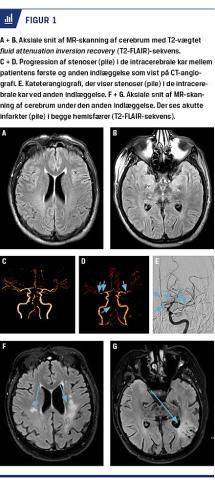

Han havde en samlet National Institute of Health Stroke Scale (NIHSS)-score på 6 ved ankomsten til sygehuset ca. to en halv time efter symptomdebut. En akut MR-skanning af cerebrum viste normale forhold (Figur 1A + B). Grundet vedvarende fokale kliniske symptomer blev patienten trombolysebehandlet. Ultralydskanning og CT-angiografi af de præ- og intracerebrale kar viste multiple stenoser i a. basiliaris, hvilket blev tolket som arteriosklerose (Figur 1C). Patienten oplevede nærkomplet klinisk remission, og en kontrol MR-skanning af cerebrum viste fortsat normale parenkymforhold. Der blev påbegyndt profylaktisk pladehæmmende behandling i form af clopidogrel, og patienten blev udskrevet til opfølgning.

Han blev imidlertid genindlagt fem uger senere pga. forbigående neurologiske udfald. En akut MR-skanning af cerebrum (med diffusion, fluid attenuation inversion recovery (T2 FLAIR)- og T2*-sekvenser) viste fortsat normale forhold. Der blev på ny foretaget CT-angiografi og ultralydskanning af de intracerebrale kar, og der sås progression af de tidligere beskrevne stenoser (Figur 1D). Man supplerede med regelret kateterangiografi, der viste multiple stenoser »som perler på en snor« og affektion af samtlige vaskulære områder, hvilket er karakteristisk for cerebral vaskulitis (Figur 1E). Der blev igangsat en bred udredning af mulige underliggende årsager til cerebral vaskulitis. Clopidogrel blev pauseret mhp. lumbalpunktur. Under indlæggelsen progredierede patientens symptomer imidlertid hurtigt til højresidig hemiparalyse og svær global afasi. En akut MR-skanning af cerebrum viste nu akutte infarkter i begge hemisfærer (Figur 1F og 1G). Man påbegyndte behandling med højdosissteroid og empirisk aciclovir. Der blev foretaget lumbalpunktur på vital indikation. Undersøgelsen viste mononukleær pleocytose på 43 × 106/l, øget CSV-proteinniveau på over 6 g/l og øget immunglobulin (Ig)G i spinalvæsken på over 1 g/l. Der blev påvist intratekal IgG-antistofdannelse mod borrelia, og patienten blev behandlet med intravenøst (i.v.) givet ceftriaxon (2 g × 1 dagligt). Hans tilstand progredierede ikke yderligere efter påbegyndelse af den antibiotiske behandling.